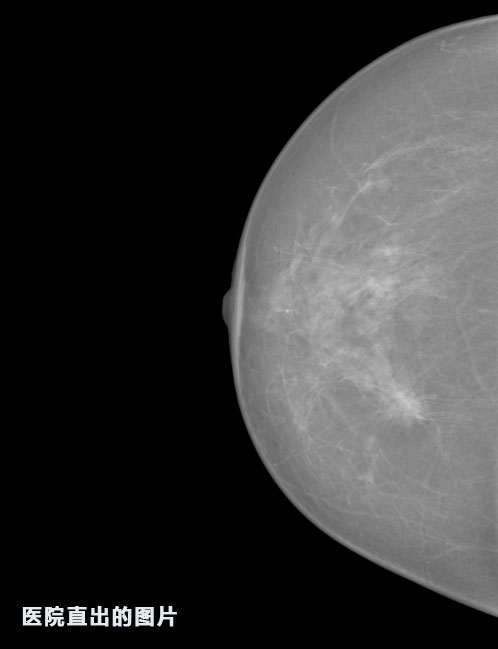

英特健康A(chǔ)I深度學(xué)習(xí)醫(yī)療圖像識(shí)別系統(tǒng)案例_乳腺

識(shí)別報(bào)告:

1.發(fā)現(xiàn)良性鈣化,可能性為19.88%---位置框指數(shù):[1796.0867 1359.8237 2058.1372 1582.5334]

2.發(fā)現(xiàn)惡意鈣化的可能性為15.18%---位置框指數(shù):[1789.4733 1365.9951 2063.7698 1576.0613]

3.發(fā)現(xiàn)惡意鈣化的可能性為12.45%---位于框指數(shù):[1859.3987 1422.3184 2006.5494 1528.2698]